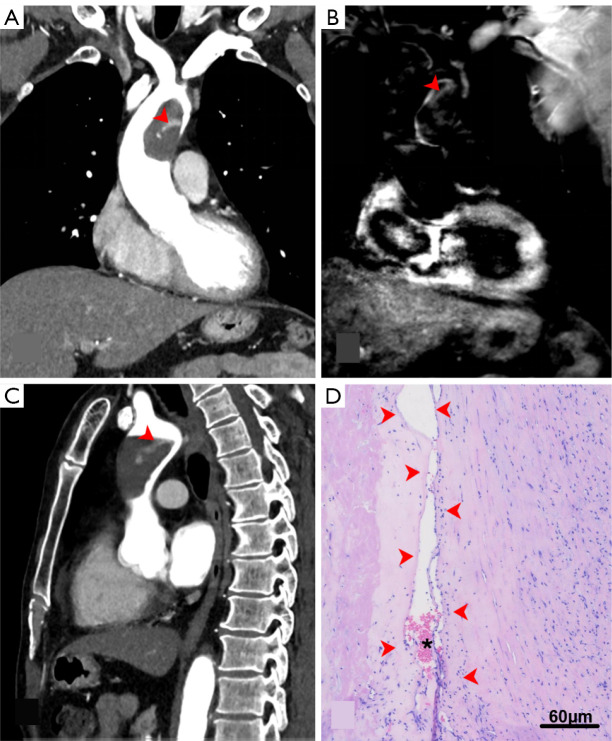

Quantitative characterization of composition heterogeneity in complex aortic thrombus using cardiac magnetic resonance: a case description.

使用心脏磁共振定量表征复杂主动脉血栓的组成异质性:一个病例描述。